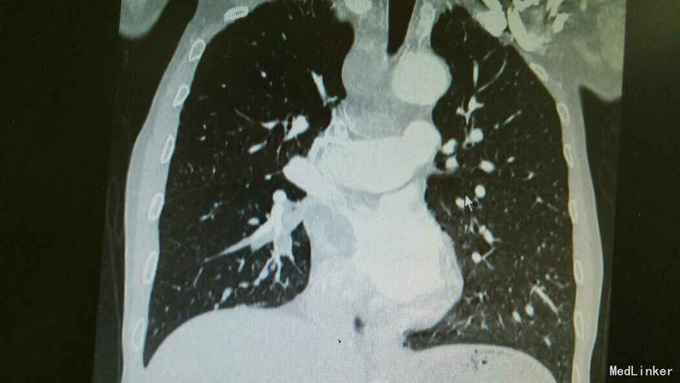

主诉:活动后气促,胸闷1年,消瘦8月余。 病史:患者1年前无明显诱因出现活动后气促,胸闷,主要为胸骨段,爬坡可诱发,伴有咳嗽,白色粘痰。伴有体重下降。

查体:慢性病容,桶状胸,双肺呼吸音粗,右下肺可闻及少量细湿罗音。 辅查:胸部CT:考虑右下肺中央型肺癌并癌性空洞形成,右下肺阻塞性肺炎 ,右下肺动静脉受累,纵隔,双侧肺门多发淋巴结肿大。

诊断:中央型肺癌并阻塞性肺炎。 治疗:入院予以抗感染,止咳化痰等治疗。

随访+讨论:患者肺癌已经为晚期,失去治疗时机,目前只能予以抗感染及对症处理。